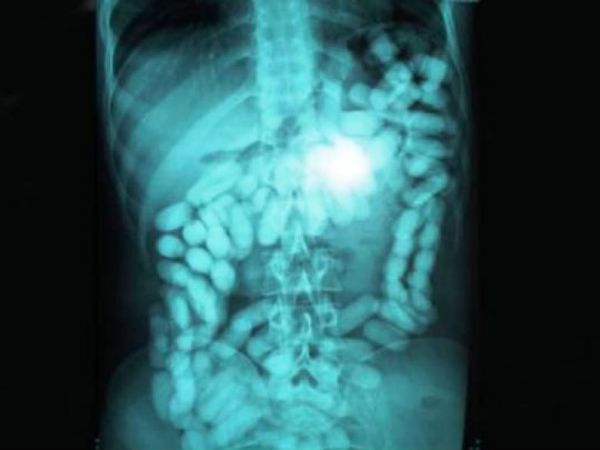

Да, глотать столовое серебро — дорогое удовольствие. А как насчет 78 серебряных ложек, которые проглотила 52-летняя женщина в Нидерландах?